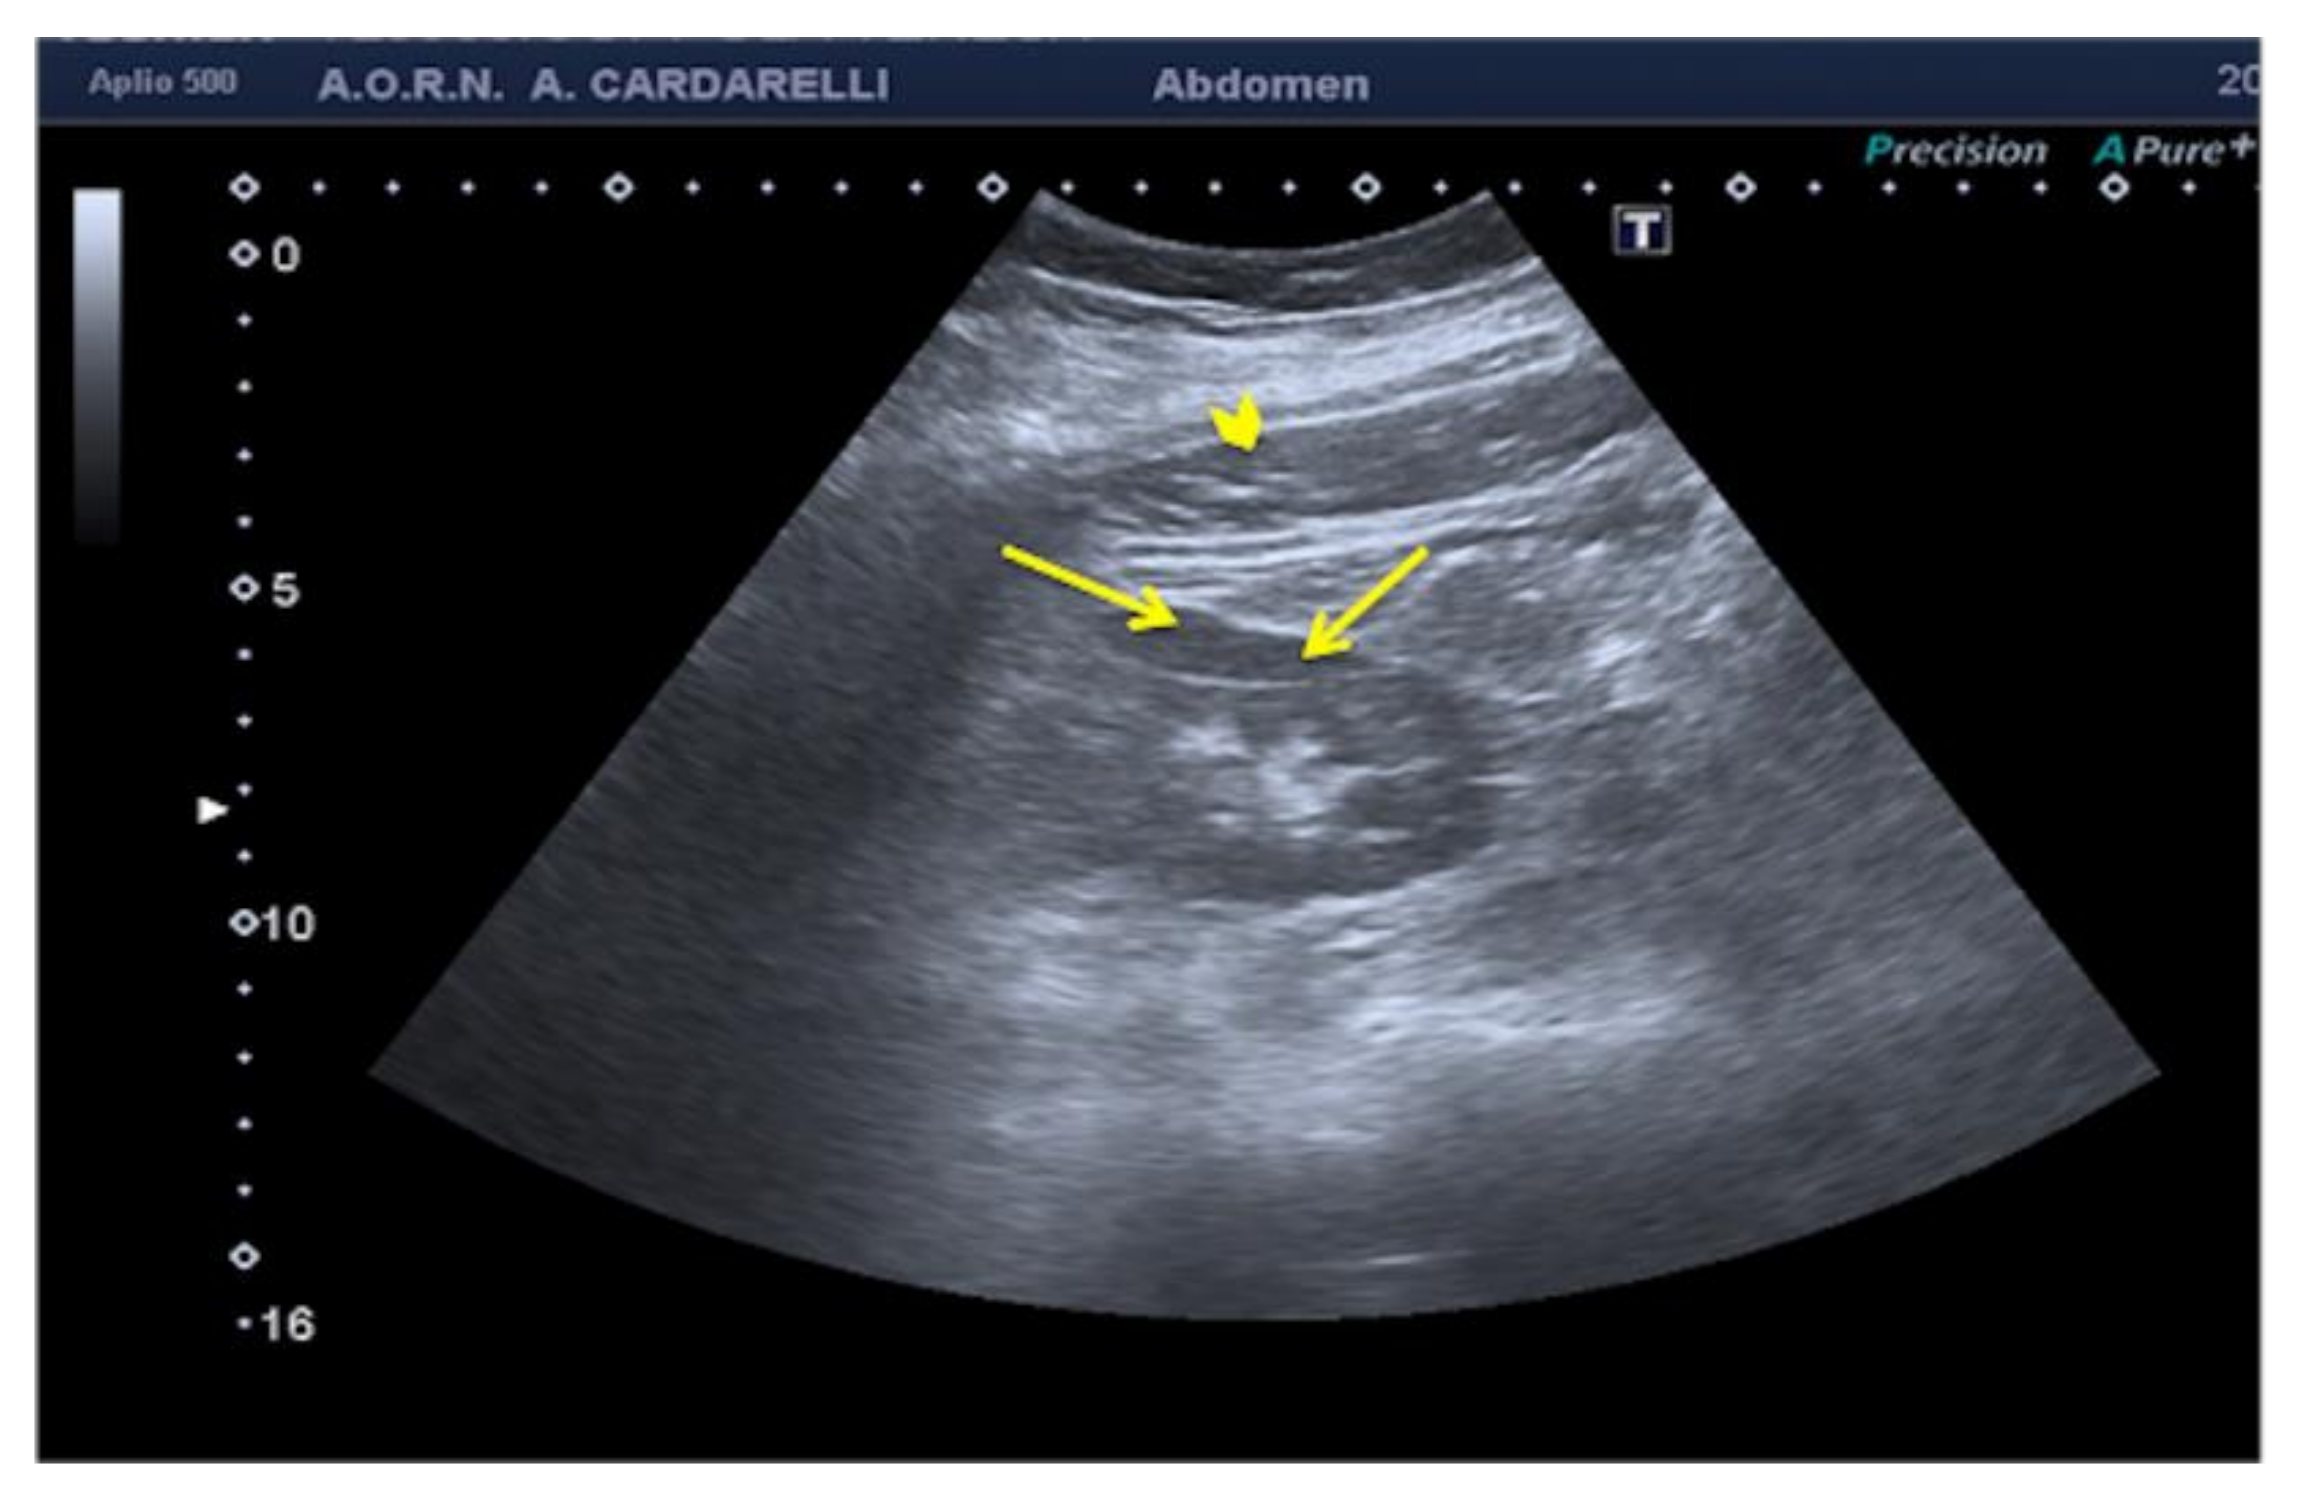

3.1.7. Anisotropy